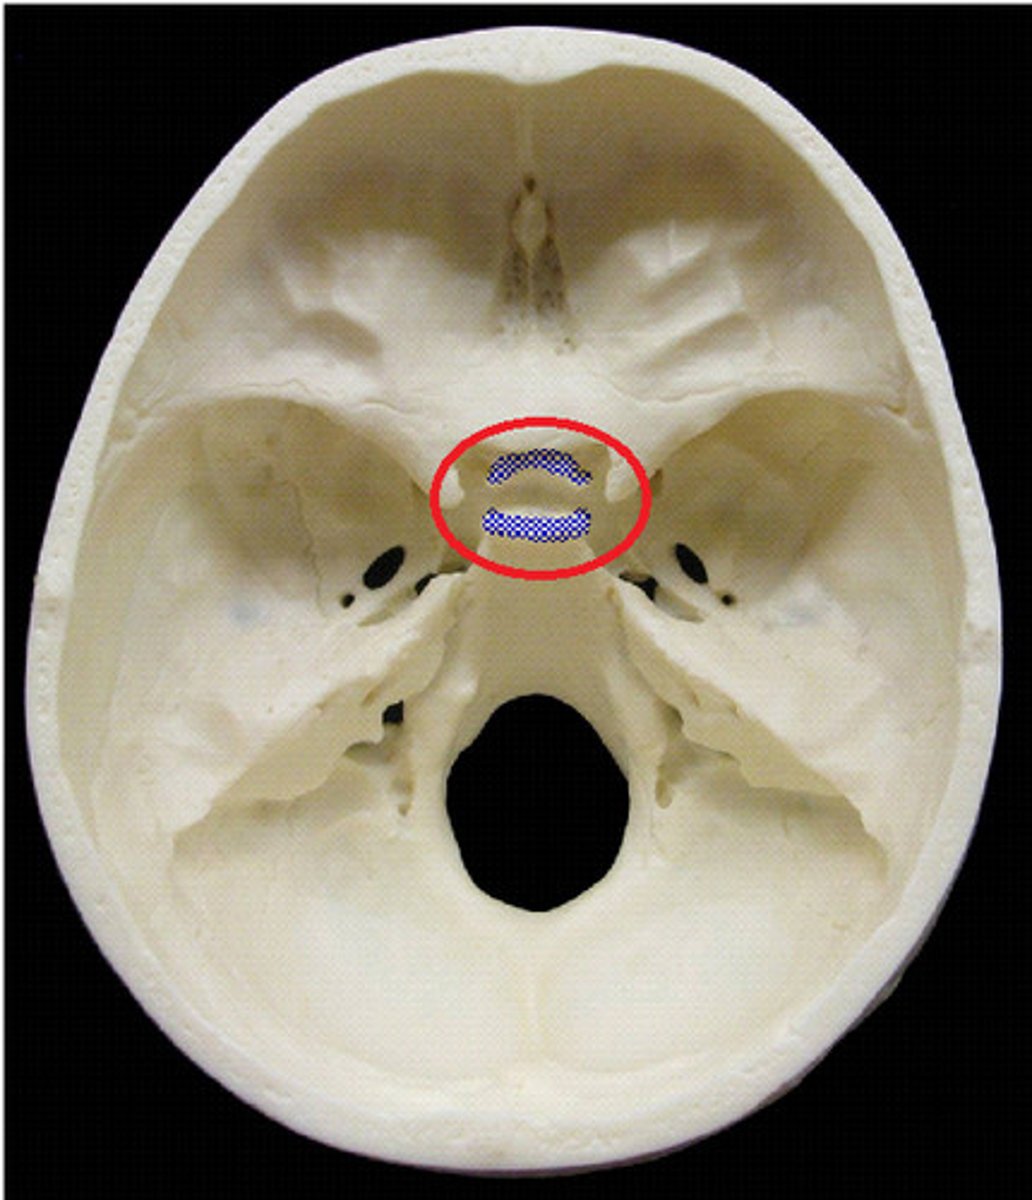

anterior cranial fossa

middle cranial fossa

posterior cranial fossa

cribriform plate

crista galli

sella turcica

tuberculum sellae

dorsum sellae

posterior clinoid processes

optic foramen

clivus